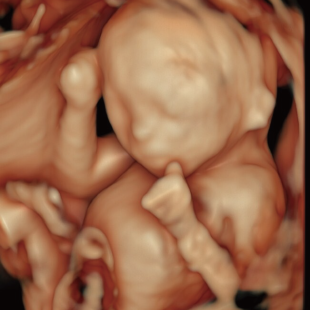

Voluson Expert 22®(GEHealthcare)という産婦人科領域におけるハイエンド超音波診断装置を使用しています。 従来機種と比べ、より高精細な画像描出性能と高度な解析機能を備えており、 胎児の発育や形態をより詳細に観察することが可能です。